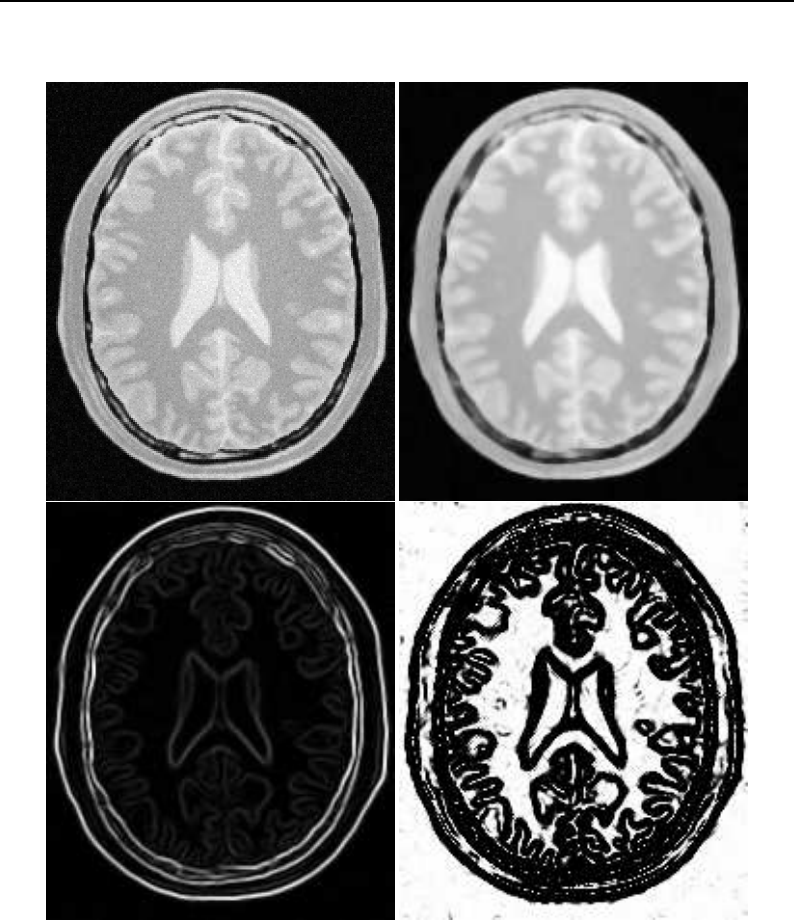

The Insight Toolkit (ITK) is an open-source, cross-platform system for medical image processing. It

provides medical imaging researchers with an extensive suite of leading-edge algorithms for

registering, segmenting, analyzing, and quantifying medical data. It is used in thousands of research

and commercial applications, from major labs to individual innovators.

The National Library of Medicine Insight Segmentation and Registration Toolkit, shortened as the

Insight Toolkit (ITK), is an open-source software toolkit for performing registration and segmenta-

tion. Segmentation is the process of identifying and classifying data found in a digitally sampled

representation. Typically the sampled representation is an image acquired from such medical instru-

mentation as CT or MRI scanners. Registration is the task of aligning or developing correspondences

between data. For example, in the medical environment, a CT scan may be aligned with a MRI scan